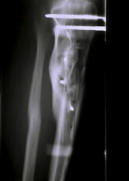

(1998) Bild 1 Komplizierter Splitterbruch vor klinischer Versorgung, Bild 2 vor Therapiebeginn. Bild 3 - 8 Heilungsverlauf.

Bild 1 Komplizierter Splitterbruch vor klinischer Versorgung,

Bild 2 vor Therapiebeginn. Bild 3 - 8 Heilungsverlauf.

(1998) Bild 1 Komplizierter Splitterbruch vor klinischer Versorgung,

Bild 2 vor Therapiebeginn. Bild 3 - 8 Heilungsverlauf.